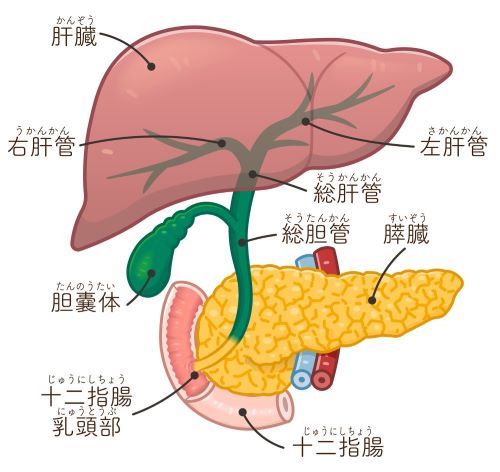

後に、彼は腰痛の治療を求めて私のもとを訪れました。彼は中医学の鍼治療で痛みを和らげたいと考えていました。しかし、治療中に彼がわずかに黄疸を発症していることに気づき、内科医の診察を勧めました。

検査の結果、李さんは糖尿病や椎間板ヘルニアではなく、初期の膵臓がんであることが判明しました。彼の膵臓の腫瘍は胆のうに近接しており、黄疸を引き起こしていました。